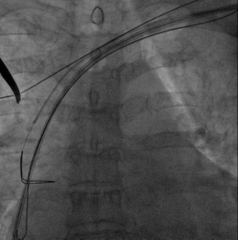

AP

LAO45

RAO30

固定左室电极,连接CRTD(DTBC2QQ),手术最终影像